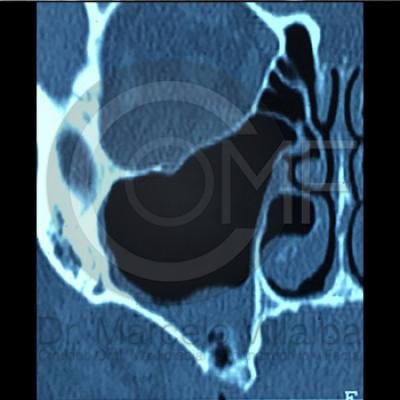

Comunicación en Seno Maxilar

Comunicacion Seno Maxilar 4